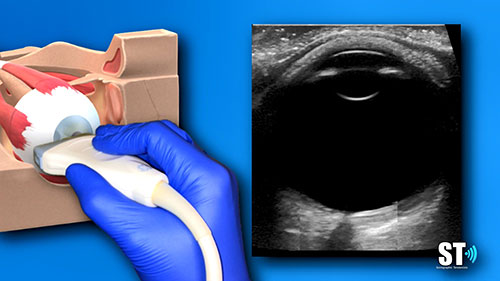

类别:眼视光技术

简介:Second Sight公司将人工视觉引入大脑,研发Orion视觉皮层假体系统,目前该系统正在六个盲人身上进行测试。